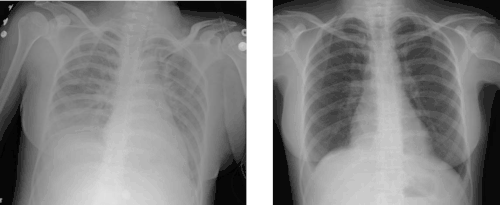

| Chest x-ray of person with severe ARDS demonstrating widespread "ground-glass" appearing opacities in both lungs. | |

Medical imaging

Radiologic imaging has long been a criterion for diagnosis of ARDS. Original definitions of ARDS specified that correlative chest X-ray findings were required for diagnosis, the diagnostic criteria have been expanded over time to accept CT and ultrasound findings as equally contributory. Generally, radiographic findings of fluid accumulation (pulmonary edema) affecting both lungs and unrelated to increased cardiopulmonary vascular pressure (such as in heart failure) may be suggestive of ARDS. Ultrasound findings suggestive of ARDS include the following: